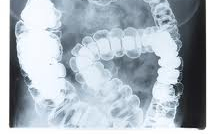

Új kezelés nyújthat enyhülést a gyulladásos bélbetegségben, a Chron-szindrómában, valamint a vastagbélgyulladásban szenvedők számára – állítják amerikai kutatók, akiknek felfedezéséről a hostednews számol be.

A Vedolizumab egy intravénás anitest gyógyszer, ami reményt ad annak a közel négymillió embernek, akik az említett autoimmun betegségek valamelyikében szenvednek. A kezelés hatására annyira gyógyultak a páciensek, hogy abbahagyhatták a prednisolon nevű gyógyszer szedését, amelyet mindkét betegség kezelésére alkalmaznak, viszont súlyos mellékhatásai vannak.

A kísérleti vizsgálat mind a Chron-szindrómában, mind a vastagbélgyulladásban szenvedők számára ígéretesnek bizonyult akkor is, amikor más kezelési formák, mint a szteroidok vagy az immunszupresszív gyógyszerek is kudarcot vallottak.

Amennyiben az eredmények szélesebb körben is igazolódnak, és elfogadják az új terápia alkalmazását, az jelentős mértékben javíthat az érintettek életminőségén.